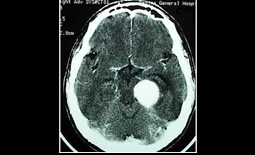

The high end technology has made accurate diagnosis possible and micro precision surgeries available for the care and cure of patients with complex neuro and spine problems has significantly improved the out come of neurological diseases. The quality of treatment in India is comparable to American, German and Thailand hospitals .The high quality at affordable cost has attracted Arabs, Omanis and Europeans to indian hospitals